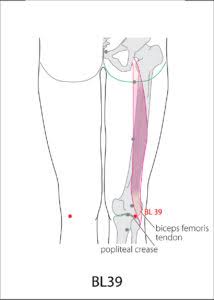

Lokasi Titik BL39 (Weiyang)

Titik BL39 terletak di bagian belakang lutut, tepatnya di sisi lateral dari tendon otot semitendinosus, pada lipatan popliteal (belakang lutut), sejajar dengan titik BL40. Titik ini dikenal sebagai “Lower He-Sea point” dari meridian Sanjiao (Triple Energizer/Triple Burner) dalam pengobatan Tiongkok.